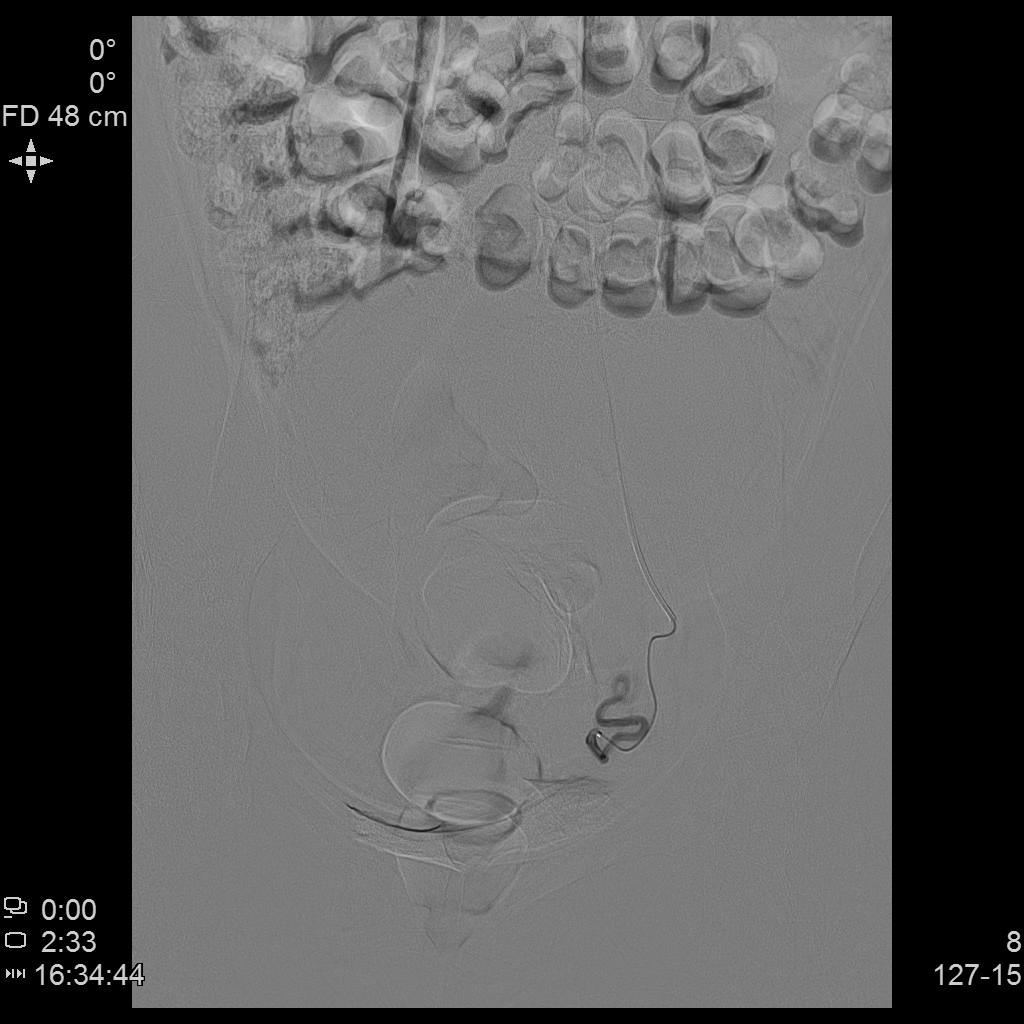

从手上扎针插管即可治肌瘤!——经桡动脉入路子宫动脉栓塞术

中年女性,发现子宫肌瘤进行性增大5年余。复查彩超提示多发肌瘤,较前明显增大(最大者直径近10cm)。近半年尿频、尿急症状进行性加重,考虑增大的子宫肌瘤压迫膀胱所致。

- MRI显示多发子巨大宫肌瘤,压迫膀胱。

- 经左侧桡动脉穿刺置入导管鞘,将导管送至双侧髂内动脉,再使用微导管超选择性插管至双侧子宫动脉主干远端。与传统股动脉入路进行手术疗效并无差异,仅是血管入路不同,其余手术操作相同,最终插管终点仍为子宫动脉主干远端。

- 术后桡动脉压迫止血8小时。

- 术后3个月复查MRI显示多发肌瘤明显坏死、缩小。相关症状已基本消失。